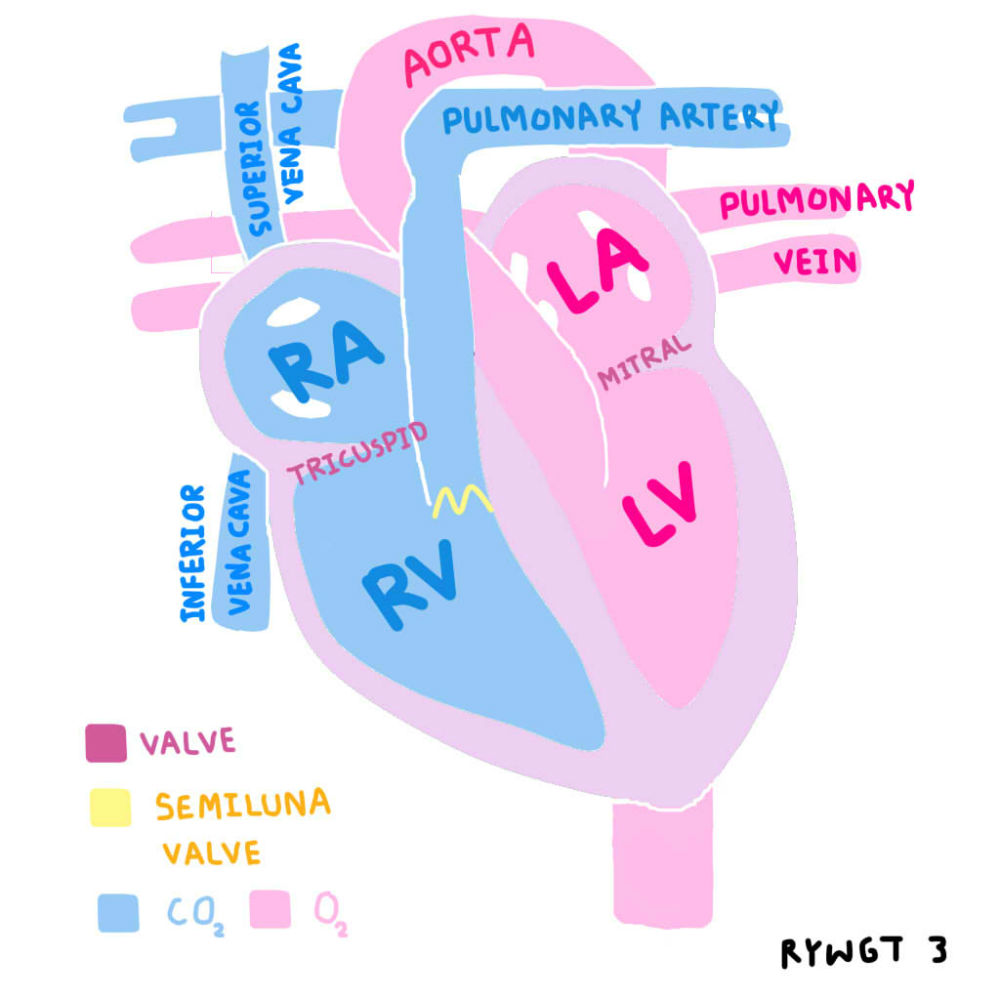

37,900+ การไหลเวียนของเลือด ภาพถ่ายสต็อก รูปภาพ และภาพปลอดค่าลิขสิทธิ์ … หัวใจกับการไหลเวียนของเลือด – ระบบไหลเวียนโลหิต

หัวใจกับการไหลเวียนของเลือด – ระบบไหลเวียนโลหิต ม.2 ระบบหมุนเวียนเลือด | Science – Quizizz

ม.2 ระบบหมุนเวียนเลือด | Science – Quizizz ระบบไหลเวียนเลือด: หัวใจ

การไหลเวียนของปอด ภาพประกอบสต็อก – ดาวน์โหลดรูปภาพตอนนี้ – ปอด – ระบบ … Heart Diagram กายวิภาคศาสตร์ร่างกายมนุษย์ระบบไหลเวียนโลหิตหัวใจ …

แผนภาพแสดงการไหลเวียนของเลือดของหัวใจมนุษย์ ภาพประกอบสต็อก – ดาวน์โหลด … ระบบหัวใจและหลอดเลือด ระบบไหลเวียนโลหิต ภาพประกอบ ภาพสต็อก รูปภาพ และ …